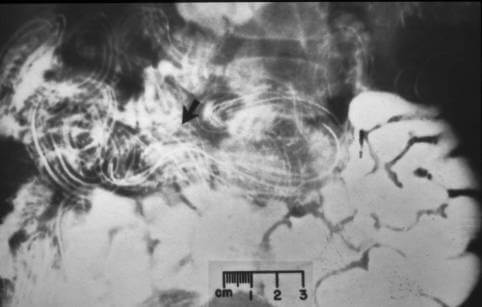

Gliste u žuči:

Prvo, neke vrste pantljičara mogu da prouzrokuju rak. Pantljičara se razboli. A onda se maligne ćelije šire po celom telu. Ovaj slučaj se dešava kad se larve helminta šire iz probavnog trakta po limfnim čvorovima. Na ovakav način se pretvaraju u tumor neverovatnom brzinom. Ljudi koji imaju parazite mogu da umru samo nakon nekoliko meseci. Baš je ove sedmice jedna osoba umrla od takvog tumora.

Na sredini slike: melanom koji su uzrokovali paraziti.

"Imamo foto arhivu: fotografije snimljene za vreme autopsije kada smo otkrili različite parazite u ljudskim organima. Evo nekoliko primera. Upozoravam vas, užasni su".